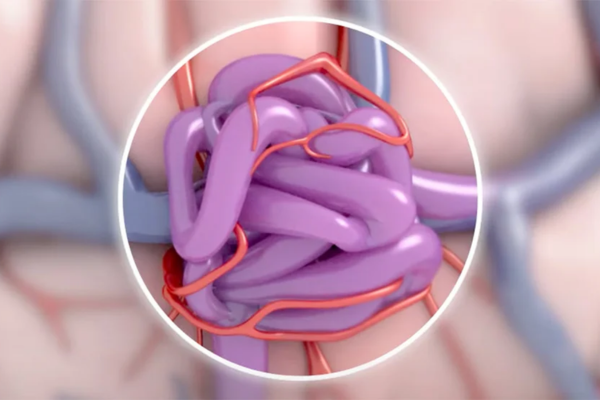

Cranial vascular malformations cause abnormal connections between arteries and veins, leading to bleeding, seizures, or neurological deficits.

Embolization blocks these abnormal vessels using specialized materials, restoring normal blood flow and reducing the risk of life-threatening brain hemorrhage.

Blocks abnormal blood vessel connections to reduce bleeding risks, shrink the malformation, and prepare for further treatment if needed.